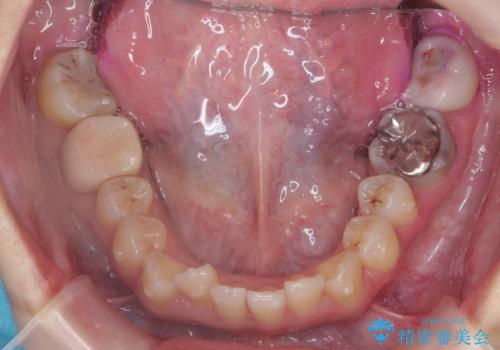

- 前歯のがたつきを主訴に来院。

保険治療の被せ物が前歯に2本あり、矯正治療で移動後にセラミックでやり替えを行っています。

右上のかみ合わせがずれていたため、インプラント矯正を行い、奥歯を後ろに下げて治療しています。